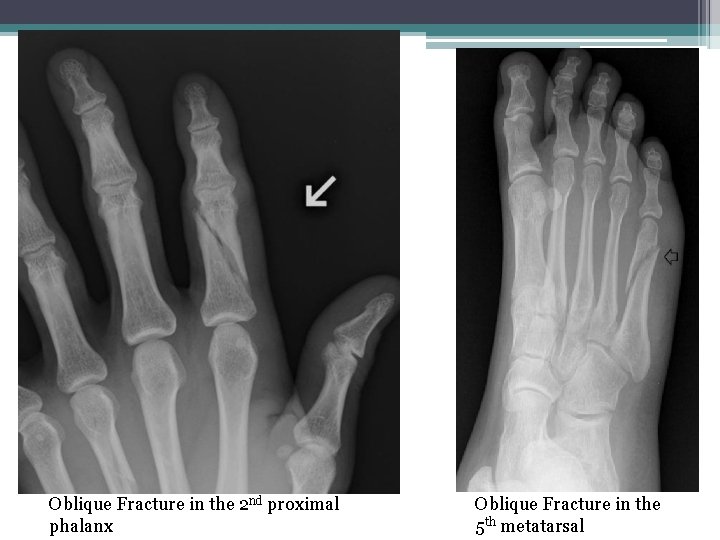

• 11 -Oblique Fractures: a fracture that is diagonal to a bone’s long axis (the break is on an angle). Oblique Displaced Non-displaced

Oblique Fracture in the 2 nd proximal phalanx Oblique Fracture in the 5 th metatarsal